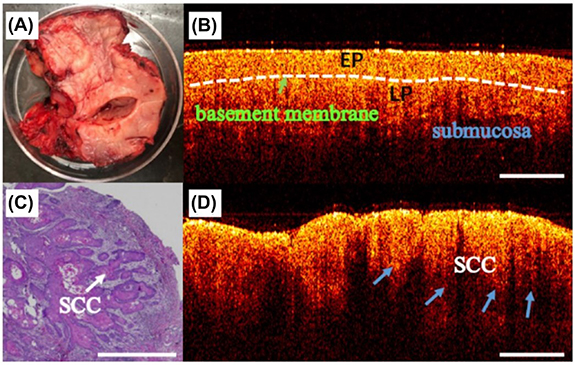

Compared to TD-OCT, FD-OCT has a higher imaging speed and signal-to-noise ratio and is less likely to be confounded by motion artifacts [150]. Spectral domain (SD-OCT) utilizes the frequency components of backscattered light to create an image of the tissue [148]. Swept source (SS-OCT) combines the capabilities of TD-OCT and SD-OCT, which has been shown to differentiate pathological oral lesions from healthy tissue (figure 6) [152–154]. However, Hamdoon et al reported that SS-OCT was inadequate in grading PMLs, and definitive identification of the basement membrane was challenging because of the limited depth of imaging [152]. Further, hyperkeratosis associated with most oral premalignancies has a degrading effect on image quality [155]. Despite these limitations, OCT has been investigated for clinical use in endoscopic procedures [156] and intraoperative imaging of oral lesions [157]. Furthermore, portable OCT systems have been developed to improve access to low resource clinical environments, which have been shown to exhibit superior diagnostic performance than COE [158].

Figure 6. (A) A photograph of an excised oral tissue sample. Optical coherence tomography images of the same sample at two different locations with (B) normal mucosa and (D) squamous cell carcinoma (SCC). (C) Histopathological image of the SCC. EP: epithelial layer and LP: lamina propria. Reproduced from [157]. CC BY 4.0. © The Author(s).

Standard image High-resolution imageImage processing algorithms have been developed to classify oral precancerous lesions by extracting quantitative parameters from OCT images. Lee et al analyzed SS-OCT image data to differentiate between normal mucosa, mild dysplasia, and moderate dysplasia in 54 patients [159]. Patients with mild oral dysplasia can reverse their condition by refraining from harmful practices that lead to cancer, such as smoking and alcohol consumption [159]. Lee et al mapped the standard deviation (SD) of the OCT signal intensity to estimate the distribution of dysplastic cells. They found that based on an SD threshold level of 70%, their method differentiated mild dysplasia from moderate dysplasia with a sensitivity of 82% and a specificity of 90% [159].